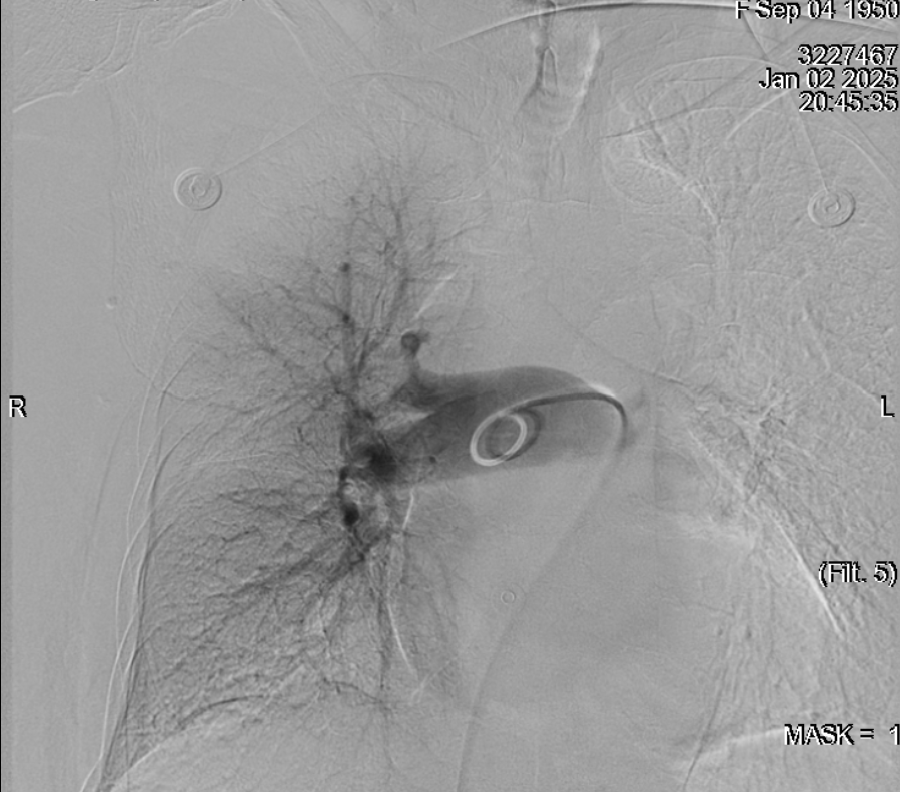

医生向患者家属沟通该疾病的潜在风险及治疗方案后,患者家属立即选择行下腔静脉滤器置入+肺动脉栓塞取栓溶栓术。 术后继续行标准抗凝治疗,抗凝5天后复查CTPT。 经过血管外科医护的精心治疗,何婆婆顺利出院了,术后继续抗凝3-6月,门诊随访既可。

肺栓塞的治疗主要包括一般治疗、药物治疗和介入治疗。对于疑似或确诊的肺栓塞患者,需要密切监测心率、呼吸、血压等变化,同时保持排便通畅,避免深静脉血栓脱落。在疾病发作期间,可以使用抗凝药物和溶栓药物进行治疗。如果病情严重,存在血流动力学不稳定、溶栓失败、主干及主要分支栓塞等情况,可以考虑介入治疗,如导管内溶栓取栓、球囊血管成形术等。